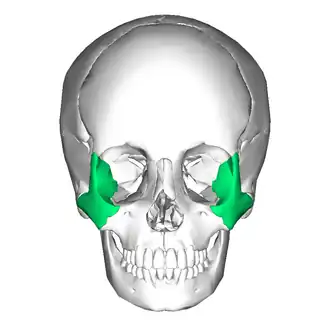

Zygomatic bone

Position of the zygomatic bone | |

In the human skull, the zygomatic bone (from Ancient Greek: ζῠγόν, romanized: zugón, lit. 'yoke'), also called cheekbone or malar bone, is a paired irregular bone, situated at the upper and lateral part of the face and forming part of the lateral wall and floor of the orbit, of the temporal fossa and the infratemporal fossa. It presents a malar and a temporal surface; four processes (the frontosphenoidal, orbital, maxillary, and temporal), and four borders.